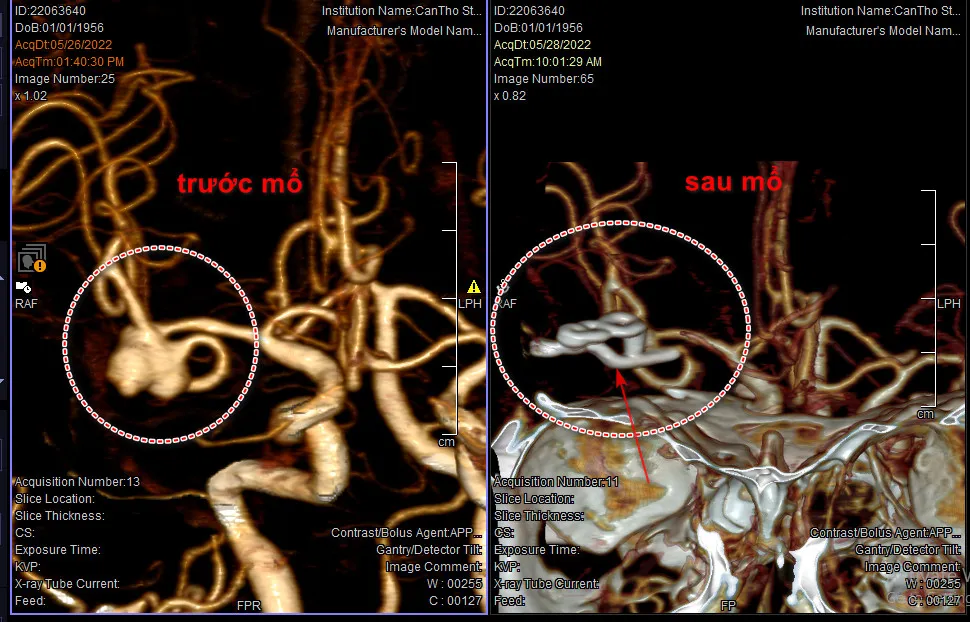

Người phụ nữ bị vỡ mạch máu não khi đang hát karaoke ảnh 2 Hình ảnh túi phình mạch máu não của bà V. trước và sau khi phẫu thuật

Sau đó, gia đình đã đưa bà V. đến Bệnh viện S.I.S Cần Thơ trong tình trạng nôn ói nhiều, kèm theo đau đầu dữ dội. Tại đây, các bác sĩ tiến hành chụp CT tìm nguyên nhân, kết quả cho thấy bà V. bị xuất huyết khoang dưới nhện do vỡ phình mạch máu não.

BS.CKI Nguyễn Quang Hưng, Trưởng đơn vị Ngoại Thần kinh Bệnh viện S.I.S Cần Thơ, người trực tiếp mổ cho bà V. cho biết: Túi phình mạch máu não của bà V. có thể đã hình thành ít nhất 1 năm trước đó, vì kích thước của túi phình rất lớn. Khi hát, bệnh nhân đã gắng sức ở những khúc lên cao trào, dẫn đến huyết áp tăng lên, khiến lưu lượng máu dồn lên quá nhiều, quá giới hạn của túi phình nên túi phình bị bể.